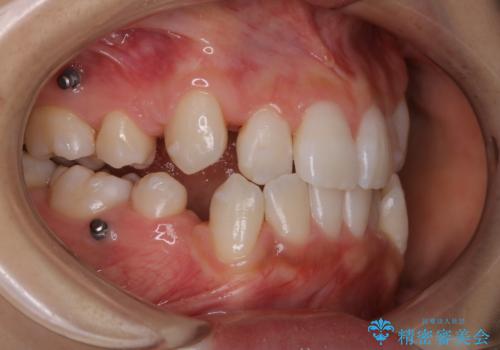

- インビザラインでのマウスピース矯正中に着色が気になるとのことでした。着色が全体的に付着していたためPMTC60分コースを行いました。

PMTC(保険外治療)は、毎日の歯磨きで落としきれない汚れや、コーヒ、紅茶・タバコのヤニなどの着色も除去します。目には見えない歯と歯の間・歯肉の境目・インビザライン中はアタッチメント周囲などに残っているプラーク(歯垢)もしっかり取り除きます。PMTCでは専門的な機械や材料を使用して、徹底的に汚れを除去するため、虫歯・歯周病・口臭予防などにつながります。